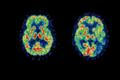

Testovaná látka dokáže redukovat plaky na mozku a zároveň zpomalovat postup demence, jejíž příčinou je v 60 procentech Alzheimerova choroba.

Mladí čeští vědci z pražské motolské nemocnice strávili čtyři měsíce v Austrálii výzkumem Alzheimerovy choroby. Neuropsycholožka Kateřina Čechová zjišťovala, jaké varianty genů zvyšují předpoklady pro rozvinutí demence, a jaké naopak fungují jako ochrana. Zároveň působila i v týmu, který zkoumá také vliv vzdělávání v pozdějším věku. Neurolog Ondřej Lerch v australském Brisbane pracoval na výzkumu, který by mohl přispět k přesnějšímu a časnějšímu odhalení rizikových pacientů. Zaměřil se na to, jak se na magnetické rezonanci projevují pacientovy problémy s orientací v prostoru. Zatímco metod, jak Alzheimera odhalit včas, přibývá, lék, který by chorobu vyléčil, zatím chybí.